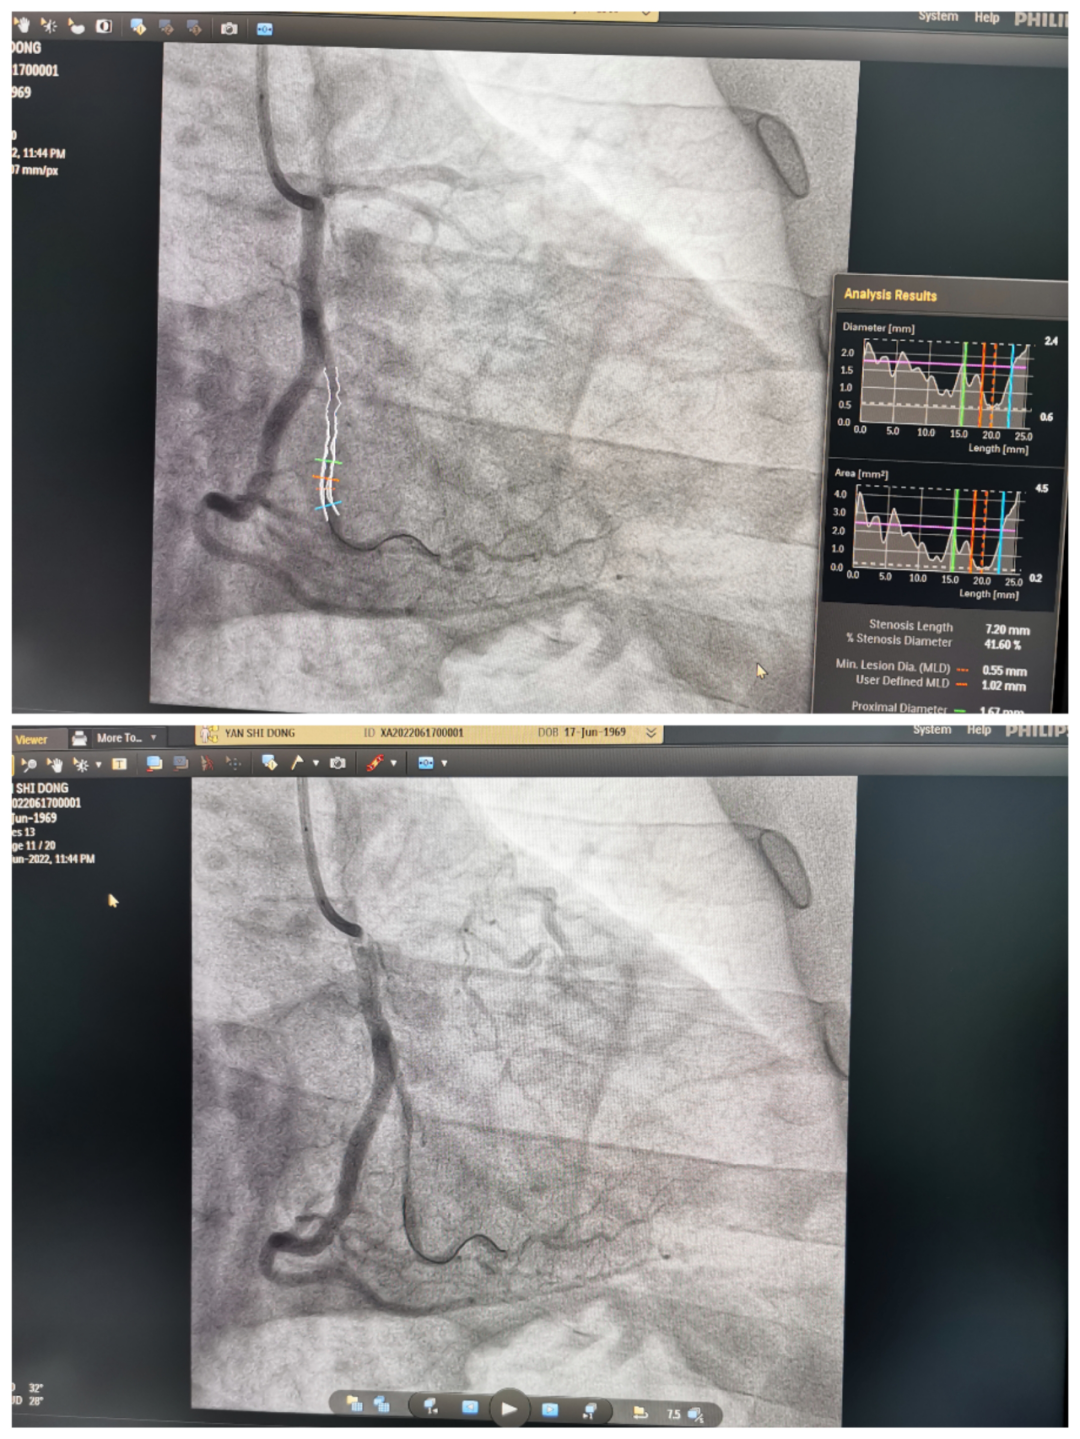

53岁的张大爷,在家突然感到胸口出现难以忍受的疼痛并且瞬间全身出汗,症状持续几小时无缓解,其家属赶紧送来我院急诊室,初诊断为"急性非ST段抬高型心肌梗死",正在急诊值班的医务人员立即请心血管内科会诊。

时间就是生命,为了赢得最佳的抢救时间,在取得家属知情同意后,心血管内科龙泉杉主治医师立即开通急性心梗救治绿色通道,全力投入到这场与死神的战斗中。

手术由我院心血管内科龙泉杉主治医师主刀,在梁婷护师以及放射科米枘技师的辅助下,为病人行急诊PTCA术。经过半个小时惊心动魄的抢救,成功挽救了张大爷的生命。术后,患者胸痛消失,症状缓解,安全返回病房。